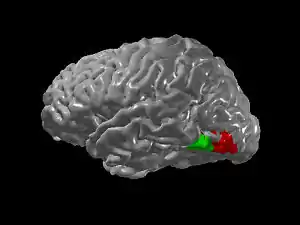

Since regions involved in the identification of letters and numbers lie adjacent to a region involved in color-processing (V4), the additional experience of seeing colors when looking at graphemes might be due to "cross-activation" of V4 (Ramachandran & Hubbard 2001). This cross-activation may arise due to a failure of the normal developmental process of pruning, which is one of the key mechanisms of synaptic plasticity, in which connections between brain regions are partially eliminated with development. Similarly, lexical → gustatory synesthesia may be due to increased connectivity between adject regions of the insula in the depths of the lateral sulcus involved in taste processing that lie adjacent to temporal lobe regions involved in auditory processing. Similarly, taste → touch synesthesia may arise from connections between gustatory regions and regions of the somatosensory system involved in processing touch. However, not all forms of synesthesia are easily explained by adjacency.

Functional neuroimaging studies using positron emission tomography (PET) and functional magnetic resonance imaging (fMRI) have demonstrated significant differences between the brains of synesthetes and non-synesthetes (although some studies failed to find such differences). The first such study used PET to demonstrate that some regions of the visual cortex (but not V4) were more active when auditory word → color synesthetes listened to words compared to tones (Paulesu et al. 1995). More recent studies using fMRI have demonstrated that V4 is more active in both word → color and grapheme → color synesthetes (Nunn et al. 2002; Hubbard et al. 2005a; Sperling et al. 2006). However, these neuroimaging studies do not have the spatial and temporal resolution to distinguish between the pruning and disinhibited feedback theories. Future research will continue to examine these questions using not only fMRI but also diffusion tensor imaging (DTI), which allows researchers to directly investigate neural connectivity in the human brain and magnetic resonance spectroscopy (MRS) which allows researchers to measure the amounts of different neurotransmitters in the brain.